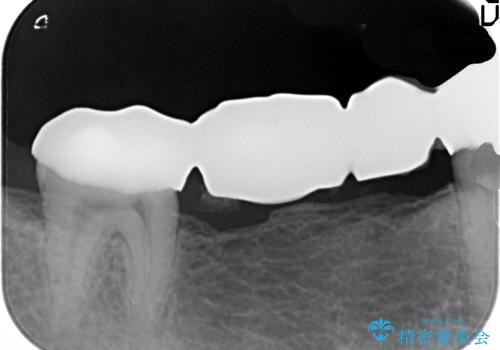

ブリッジは欠損部位の距離が長くなればなるほど支台となる歯の負担がまし、大きな咬合力負担による外傷や破折など大きなリスクにさらされます。

インプラントを用いることで残っている歯の負担も減らし、長期的な予後を見込むことができます。